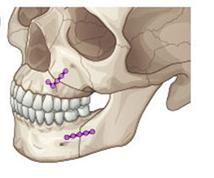

¼ºÀο¡¼ °ñ°ÝÀûÀÎ ¹®Á¦(ÁÖ°ÆÅÎ, ¹«ÅÎ, ¾È¸éºñ´ëĪ µî)¸¦ ÇØ°áÇϰíÀÚ ÇÒ °æ¿ì ±³Á¤°ú ¼ö¼úÀ» µ¿½Ã¿¡ ÇÊ¿ä·Î ÇÏ°Ô µË´Ï´Ù(±×¸²6). ÀÌ °æ¿ì ÀϹÝÀûÀ¸·Î ¼ö¼úÀ» À§ÇÑ Áغñ(¼úÀü±³Á¤) - ¼ö¼ú - ¼ö¼ú ÈÄ ±³ÇÕÈ®¸³À» À§ÇÑ ±³Á¤(¼úÈı³Á¤)ÀÇ °úÁ¤À» °ÅÄ¡°Ô µÇ´Âµ¥ Åë»óÀûÀ¸·Î 2³â ÀÌ»óÀÇ ±â°£ÀÌ ÇÊ¿äÇÕ´Ï´Ù.

| | ±×¸²6 |